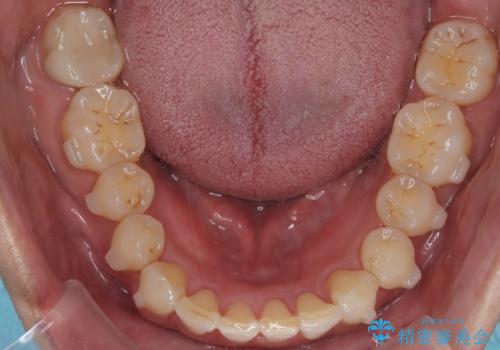

【インザライン】前歯の凸凹を治したい

- 前歯の凸凹を主訴に来院されました。

下顎位が右方に変異しており、外科矯正も提案しましたが患者様は希望されず、インビザラインにて治療を完了しております。

叢生のスペースを確保するために、臼歯部の遠心移動を行っています。

今回の治療計画は上顎の正中を顔と揃えることを優先しています。